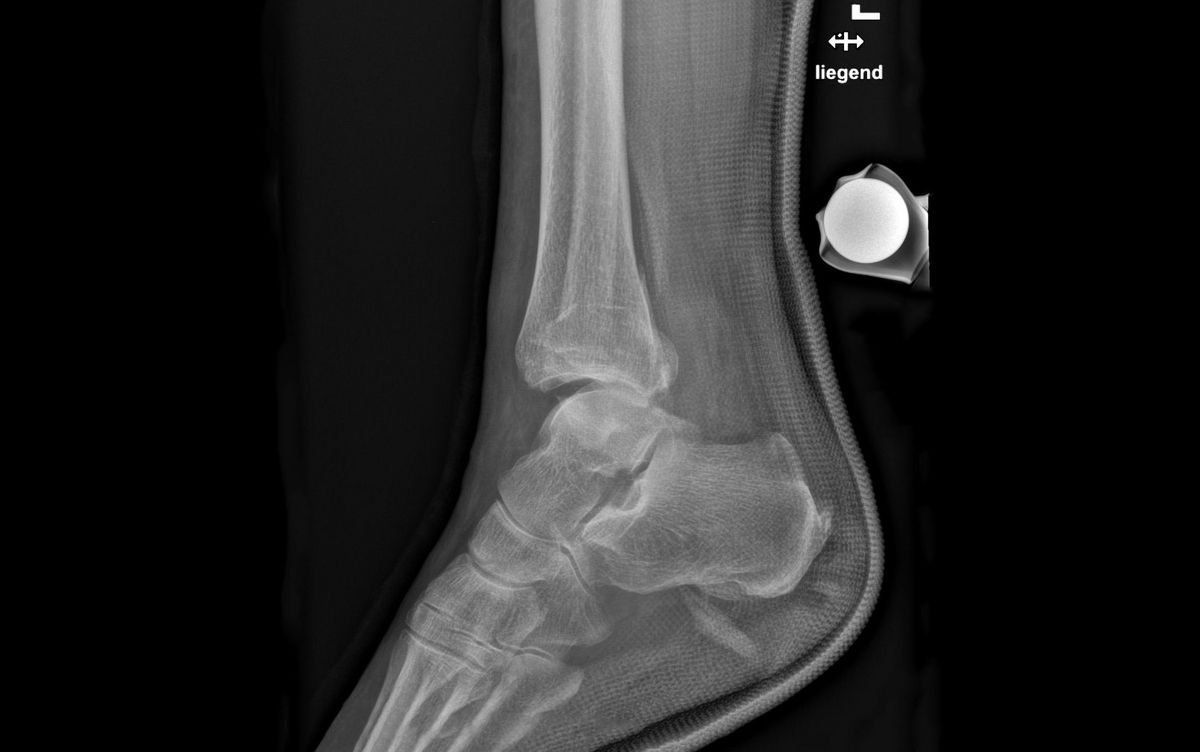

Die Schmerzen und die Schwellung über dem Aussen- und/oder Innenknöchel lassen bei der Untersuchung häufig auf eine Bandverletzung oder einen Bruch schliessen. Die definitive Diagnose wird jedoch erst anhand eines Röntgenbilds gestellt. Eine weiterführende Diagnostik mittels Magnetresonanztomographie (MRT bzw. engl. MRI für magnetic resonance imaging) bleibt unklaren Fällen mit hohem Verdacht auf zusätzliche Syndesmosenverletzung vorbehalten. Bei komplizierten Brüchen dient eine Computertomographie (CT) der besseren Erkennung oder dazu, knöcherne Zusatzverletzungen auszuschliessen.